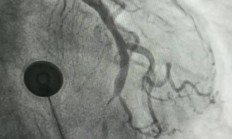

头晕、乏力竟是心梗“信号”!医生:7个非典型症状,警惕心脏问题